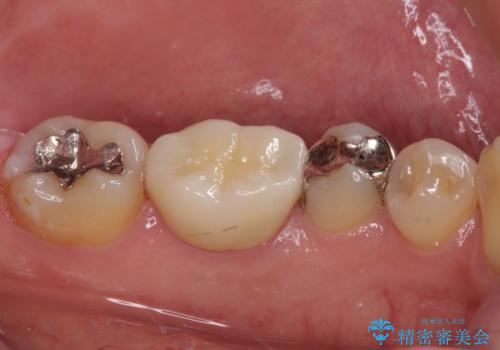

- 保険診療で装着した奥歯の白いクラウンの具合がよくないとのことで来院された患者様です。

保険診療で安価に白いクラウンが入れられるということで選択されたそうですが、装着後に痛みを感じたり、ものが挟まって不快であったりと不便が多いため、セラミッククラウンにて補綴治療を行うこととしました。

保険診療では、安価に白いクラウンを装着できる代償として、歯とクラウンの境目が不適合であったり、歯と歯の間にものが挟まりやすかったりと、不快な思いをされることがしばしばあります。

自費診療は、費用が高くなりますが、よい材料を選択したり、診療時間を十分にとったりできるため、単純に白いだけではない、良質なクラウンを装着することが可能です。